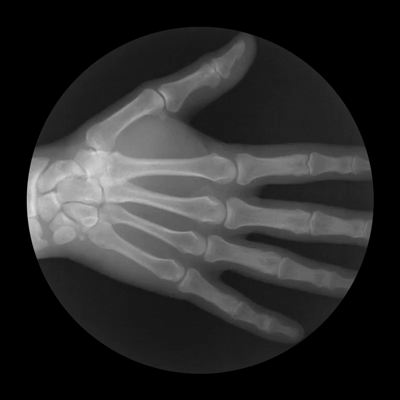

Рентген руки, сжимающейся в кулак